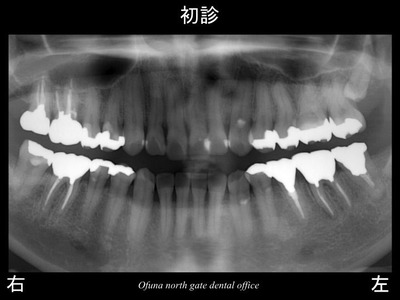

以下は初診時です。

下顎左側の奥から2番目の歯が腫れているとのことで来院された患者様です。

診査の結果、歯根破折 と診断されました。

以下が初診時のレントゲンです。

先ほどの症例と同様に歯根破折 していました。

以下が初診時です。

下顎左側の奥から2番目の歯の被せ物が取れたとのことで来院されました。

歯肉の中までおよぶ深い虫歯となっていました。

虫歯となっている歯の手前は、だいぶ前に抜歯されたそうです。